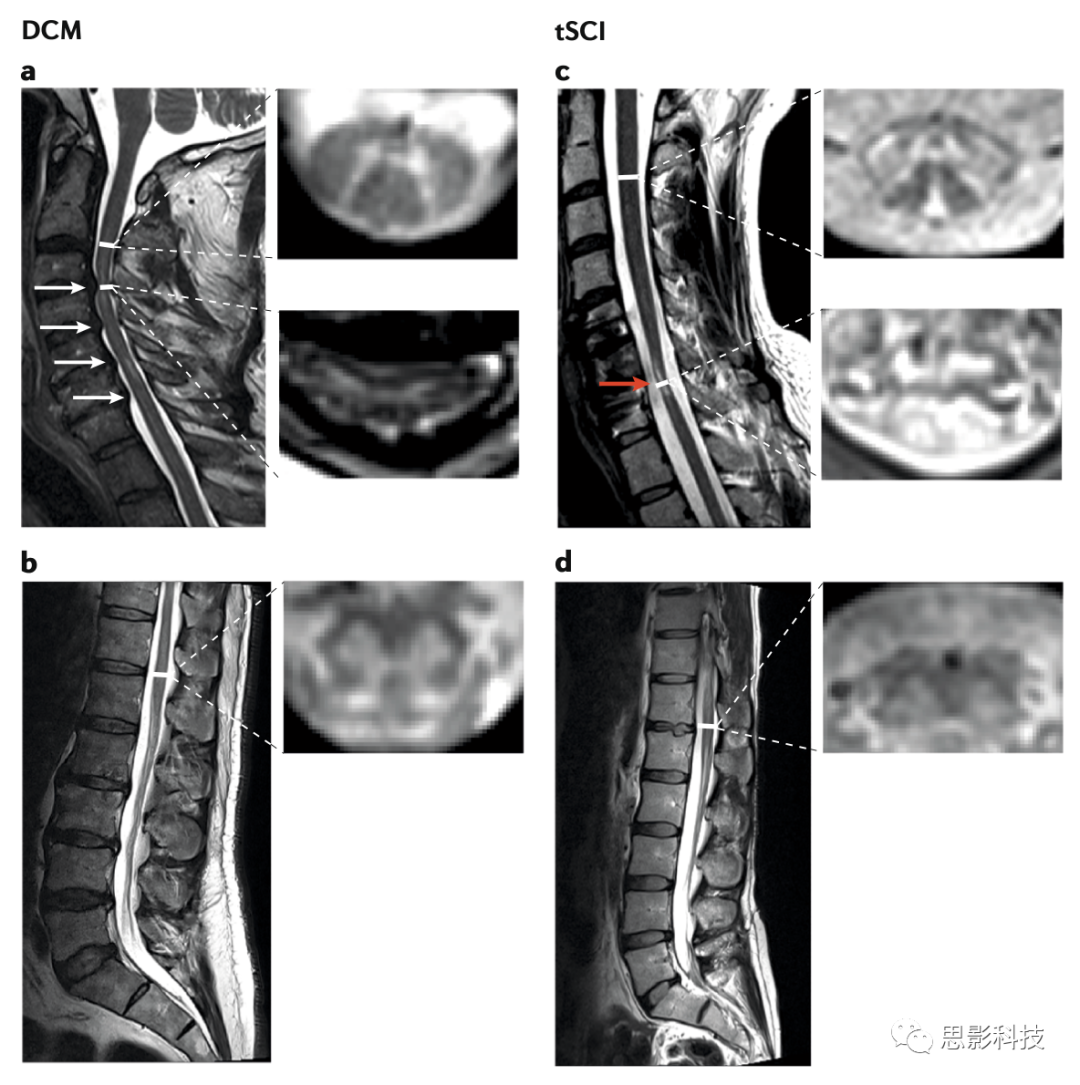

Figure 1 dcm(退行性颈脊髓病)与tSCI(外伤性脊髓损伤)主要分析部位截面图

T2加权成像以及T1加权成像这些传统的核磁成像技术都可以提供诸如脊髓的损伤原因、水平等丰富的宏观结构信息,以及识别椎间盘与韧带损伤是否存在水肿和出血等信息。传统的核磁成像技术为外科介入外伤性与非外伤性脊髓损伤的诊断工作提供了指导。如轴位的T2加权结构像可用于测量灰白质界面面积的大小和形状,从而评估组织萎缩的定量化评估标准。尽管传统的核磁成像技术已经可以捕捉如脊髓萎缩方面的灰白质形态学上的变化,但这并非特异性的,且难以揭示如髓鞘完整性与铁含量变化这种潜在的细微结构的变化,而这些细微结构的变化或许可以说明神经退化与代偿过程。